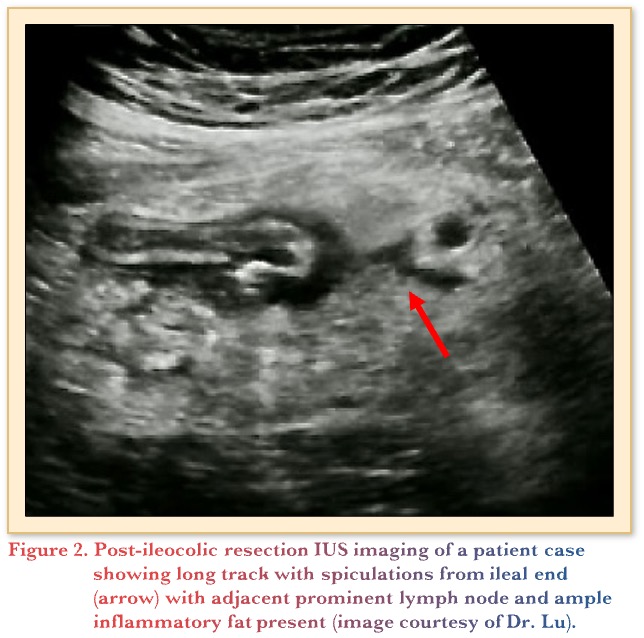

To assess its utility post-operatively, a prospective, multicenter observational cohort study evaluated the use of IUS to detect post-operative recurrence following ileocolic resection. At the 1-year mark, IUS findings were comparable with endoscopy, where wall thickening (>3mm) and FCP >50 µg/g accurately predicted recurrence, with <5% false classifications.15 Below in Figure 2 is an example of an IUS scan of a 45-year-old patient following her second surgery for fibrostenotic CD. She reported abdominal pain 2 weeks post-ileocolic resection with an end-to-side anastomosis. The treating gastroenterologist feared a possible leak. A subsequent CT scan revealed no leak and confirmed an inflammatory mass with a spiculation. The patient continued to improve following antibiotics and was started on risankizumab. Recent follow-up imaging shows complete normalization.